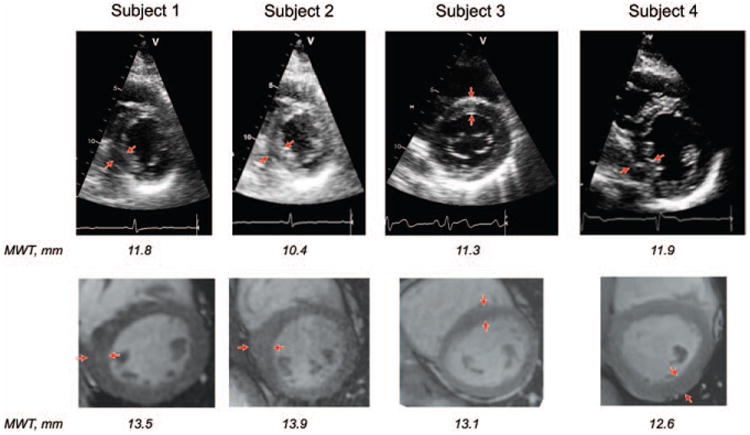

Figure 2.

Paired echocardiography (echo) and cardiac MRI (CMR) basal and midventricular short-axis images from the 4 subjects who had maximal wall thickness (MWT) ≥12 mm identified by CMR but not by echo. Regions of nonuniform increased left ventricular wall thickness are indicated by the arrows.

Figure 1 illustrates the moderate agreement between echo and CMR LV wall thickness measurements. Intracluster correlation coefficients were 0.62 for the IVS and 0.34 for the PW. CMR LV wall thickness measurements were on average ≈19% lower than echo. Of 40 subjects, both echo and CMR categorized 36 as without hypertrophy (LVH−), indicating clinical diagnostic agreement of 90% between these 2 modalities. In 3 of 40 subjects (7.5%), CMR detected mild, focal hypertrophy (measuring 13.1–13.9 mm) that did not reach the defined threshold for LVH and diagnosing HCM (13 mm) by echo. Subject 4 had borderline LVH by CMR (MWT=12.6 mm) that was just under the defined LVH threshold by echo (MWT=11.9 mm; Figure 2; Table 3). Echo and CMR were performed on the same day for these 4 subjects. In discordant subjects, the mean difference between CMR and echo measurements of maximal LV wall thickness was 1.9±1.2 mm (range, 0.7–3.5 mm). Table 3 also lists other subtle abnormalities present in these 4 subjects, including low global Ea velocities and mild ECG abnormalities.

| Echo | 10.4 (M-IS) | 11.8 (M-IS) | 11.3 (B-AS) | 11.9 (M-IS) |

| CMR | 13.9 (M-I) | 13.5 (M-IS) | 13.1 (M-AS) | 12.6 (M-PW) |

| Echo quality | Fair | Poor | Poor | Good |

| CMR quality | Fair | Good | Excellent | Good |